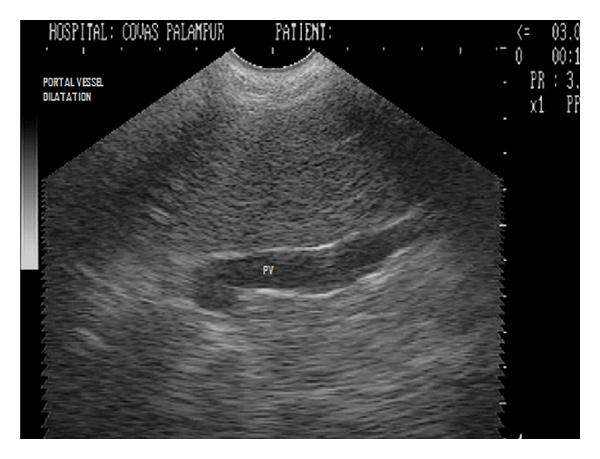

Hepatic disease is often treatable and has a predictable prognosis when a definitive diagnosis is made. The aim of clinicopathological evaluation of hepatobiliary affections is to identify and characterize hepatic damage and dysfunction, identify possible primary causes of secondary liver disease, differentiate causes of icterus, evaluate potential anaesthetic risks, assess prognosis and response to xenobiotics, and monitor response to therapy. This paper describes the different diagnostic methods and imaging techniques employed in diagnosis of hepatobiliary affections in dogs. Besides reviewing the significant clinical manifestations and imaging structural abnormalities in diagnostic approach to different hepatic affections, it also depicts radiographic, ultrasonographic, and wherever applicable, the laparoscopic characterization of different hepatic affections and target lesions encountered in clinical cases presented in the Teaching Veterinary Clinical Complex, COVAS, Palampur in the year 2007-2008.

肝病通常是可治疗的,一旦做出明确诊断,其预后是可预测的。肝胆疾病临床病理评估的目的是识别和描述肝损伤及功能障碍,确定继发性肝病可能的主要病因,鉴别黄疸的病因,评估潜在的麻醉风险,评估预后及对外源化学物质的反应,并监测治疗反应。本文描述了用于诊断犬肝胆疾病的不同诊断方法和成像技术。除了回顾不同肝病诊断方法中的重要临床表现和成像结构异常外,还描述了2007 - 2008年在帕兰普尔兽医临床综合教学中心(COVAS)出现的临床病例中不同肝病及目标病变的放射学、超声学特征,以及在适用情况下的腹腔镜特征。